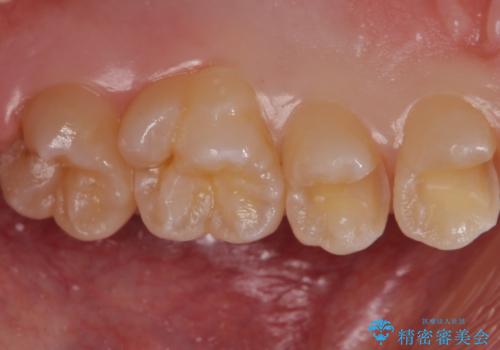

歯と歯の間の虫歯 セラミックインレーでの治療

- 検査の結果、歯と歯の間に大きな虫歯が確認されました。

セラミックでの治療をご希望されたため、セラミックインレーでの治療を行いました。

外から見て虫歯がないように見えても実は歯の中で大きく広がっていた、というケースは多く見受けられます。

症状なく進行していくことも少なくないため、定期的な検査はとても重要になってきます。

今回は残せる歯の厚みが十分確保できたため、インレーでの修復処置となりました。